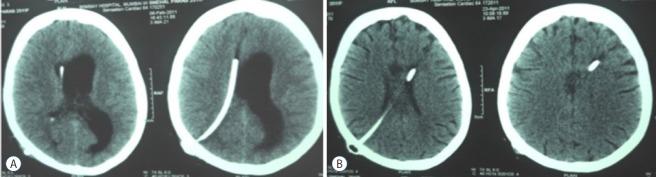

Endoscopic third ventriculostomy (ETV) has now become an accepted mode of hydrocephalus treatment in children. Varying degrees of success for the procedure have been reported depending on the type and etiology of hydrocephalus, age of the patient and certain technical parameters. Review of these factors for predictability of success, complications and validation of success score is presented.

内镜下第三脑室造瘘术(ETV)现已成为治疗儿童脑积水的一种公认方式。根据脑积水的类型和病因、患者年龄以及某些技术参数,该手术已报道有不同程度的成功率。本文对这些因素进行综述,以探讨其对手术成功率的预测性、并发症以及成功评分的验证情况。